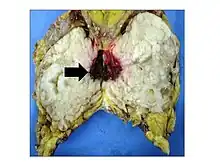

Anatomopathological results of phyllodes tumor.

Gross image of an excised phyllodes tumor.